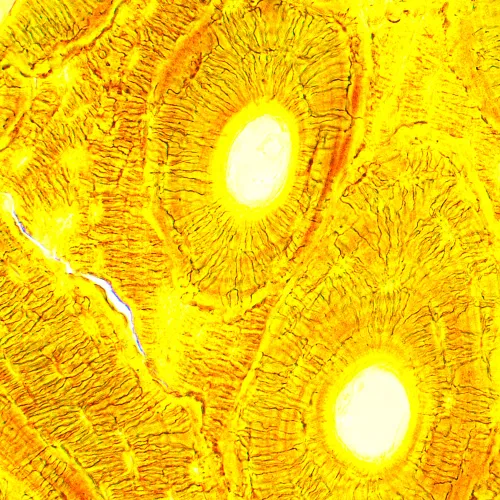

A MAGUS Bio 250B biológiai mikroszkóp egy vékony, átlátszó és áttetsző objektumok tanulmányozására használható optikai műszer. Az eszköz által alkalmazott fő mikroszkópos technika az áteső fényű világos látóterű mikroszkópia. A mikroszkóp további tartozékokkal is felszerelhető a sötét látóterű, a fáziskontrasztos és a polarizációs technikák használatához. A kiváló minőségű optika – a képességei bővítését lehetővé tévő további opciókkal –, a könnyen kezelhető mechanikai elemek és az intelligens kivitel tévén ez a mikroszkóp tökéletes választás laboratóriumi, kutatási és oktatási célokra.

Az alapkonfigurációban a mikroszkóp optikája 40-szeres és 1000-szeres közötti nagyítást biztosít. Ha szükség esetén további szemlencséket használ, azzal növelheti a nagyítási tartomány felső határát.